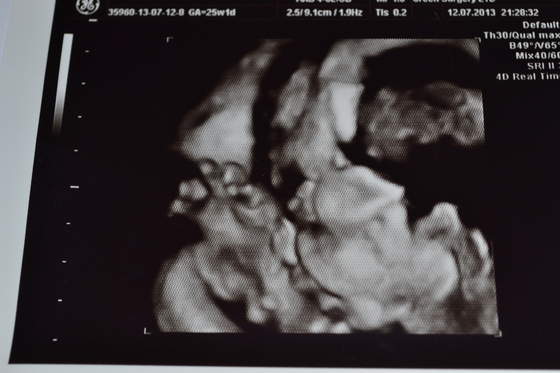

A teraz co u nas... Po usg:

Mlody dobrze, pozostal mlodym, pani gin az krzyknela! Ale ma duze jajka

Wazy... uwaga 1076 g czyli jest do przodu 2 tygodnie jesli chodzi o wymiary! Chyba musze przestac jesc owoce hehe. Ale wiadomo bylo od poczatku, ze chucherko z niego nie bedzie , bo i po kim - ja mam 176 cm a moj M 184.

Serduszko i wszystko na miejscu i ok. Lozysko nisko ale bez paniki, powinno sie jeszcze podniesc, wiec poki co porod naturalny nieskreslony

i mlody w 3d ale kiepsko widac nie podobalo mu sie i buzinke nakrywal raczkami. Widac raczke i buzie z profilu.